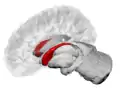

Caudate nucleus within the skull

The caudate nuclei are located near the center of the brain, sitting astride the thalamus. There is a caudate nucleus within each hemisphere of the brain. Individually, they resemble a C-shape structure with a wider "head" (caput in Latin) at the front, tapering to a "body" (corpus) and a "tail" (cauda). Sometimes a part of the caudate nucleus is referred to as the "knee" (genu).[7] The caudate head receives its blood supply from the lenticulostriate artery while the tail of the caudate receives its blood supply from the anterior choroidal artery.[8]

Transverse view of the caudate nucleus from a structural MR image

The head and body of the caudate nucleus form part of the floor of the anterior horn of the lateral ventricle. After the body travels briefly towards the back of the head, the tail curves back toward the anterior, forming the roof of the inferior horn of the lateral ventricle. This means that a coronal (on a plane parallel to the face) section that cuts through the tail will also cross the body and head of the caudate nucleus.